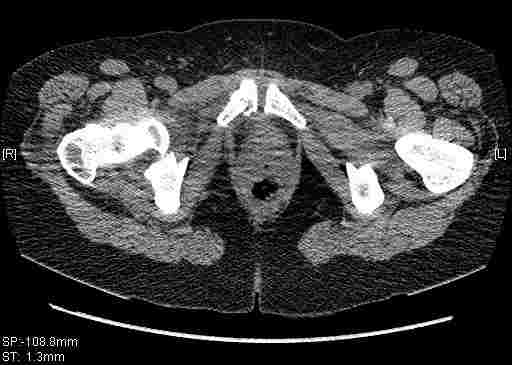

[Ortho] [2/2] Re: Т-образный перелом вертлужной впадины

Остальные срезы.